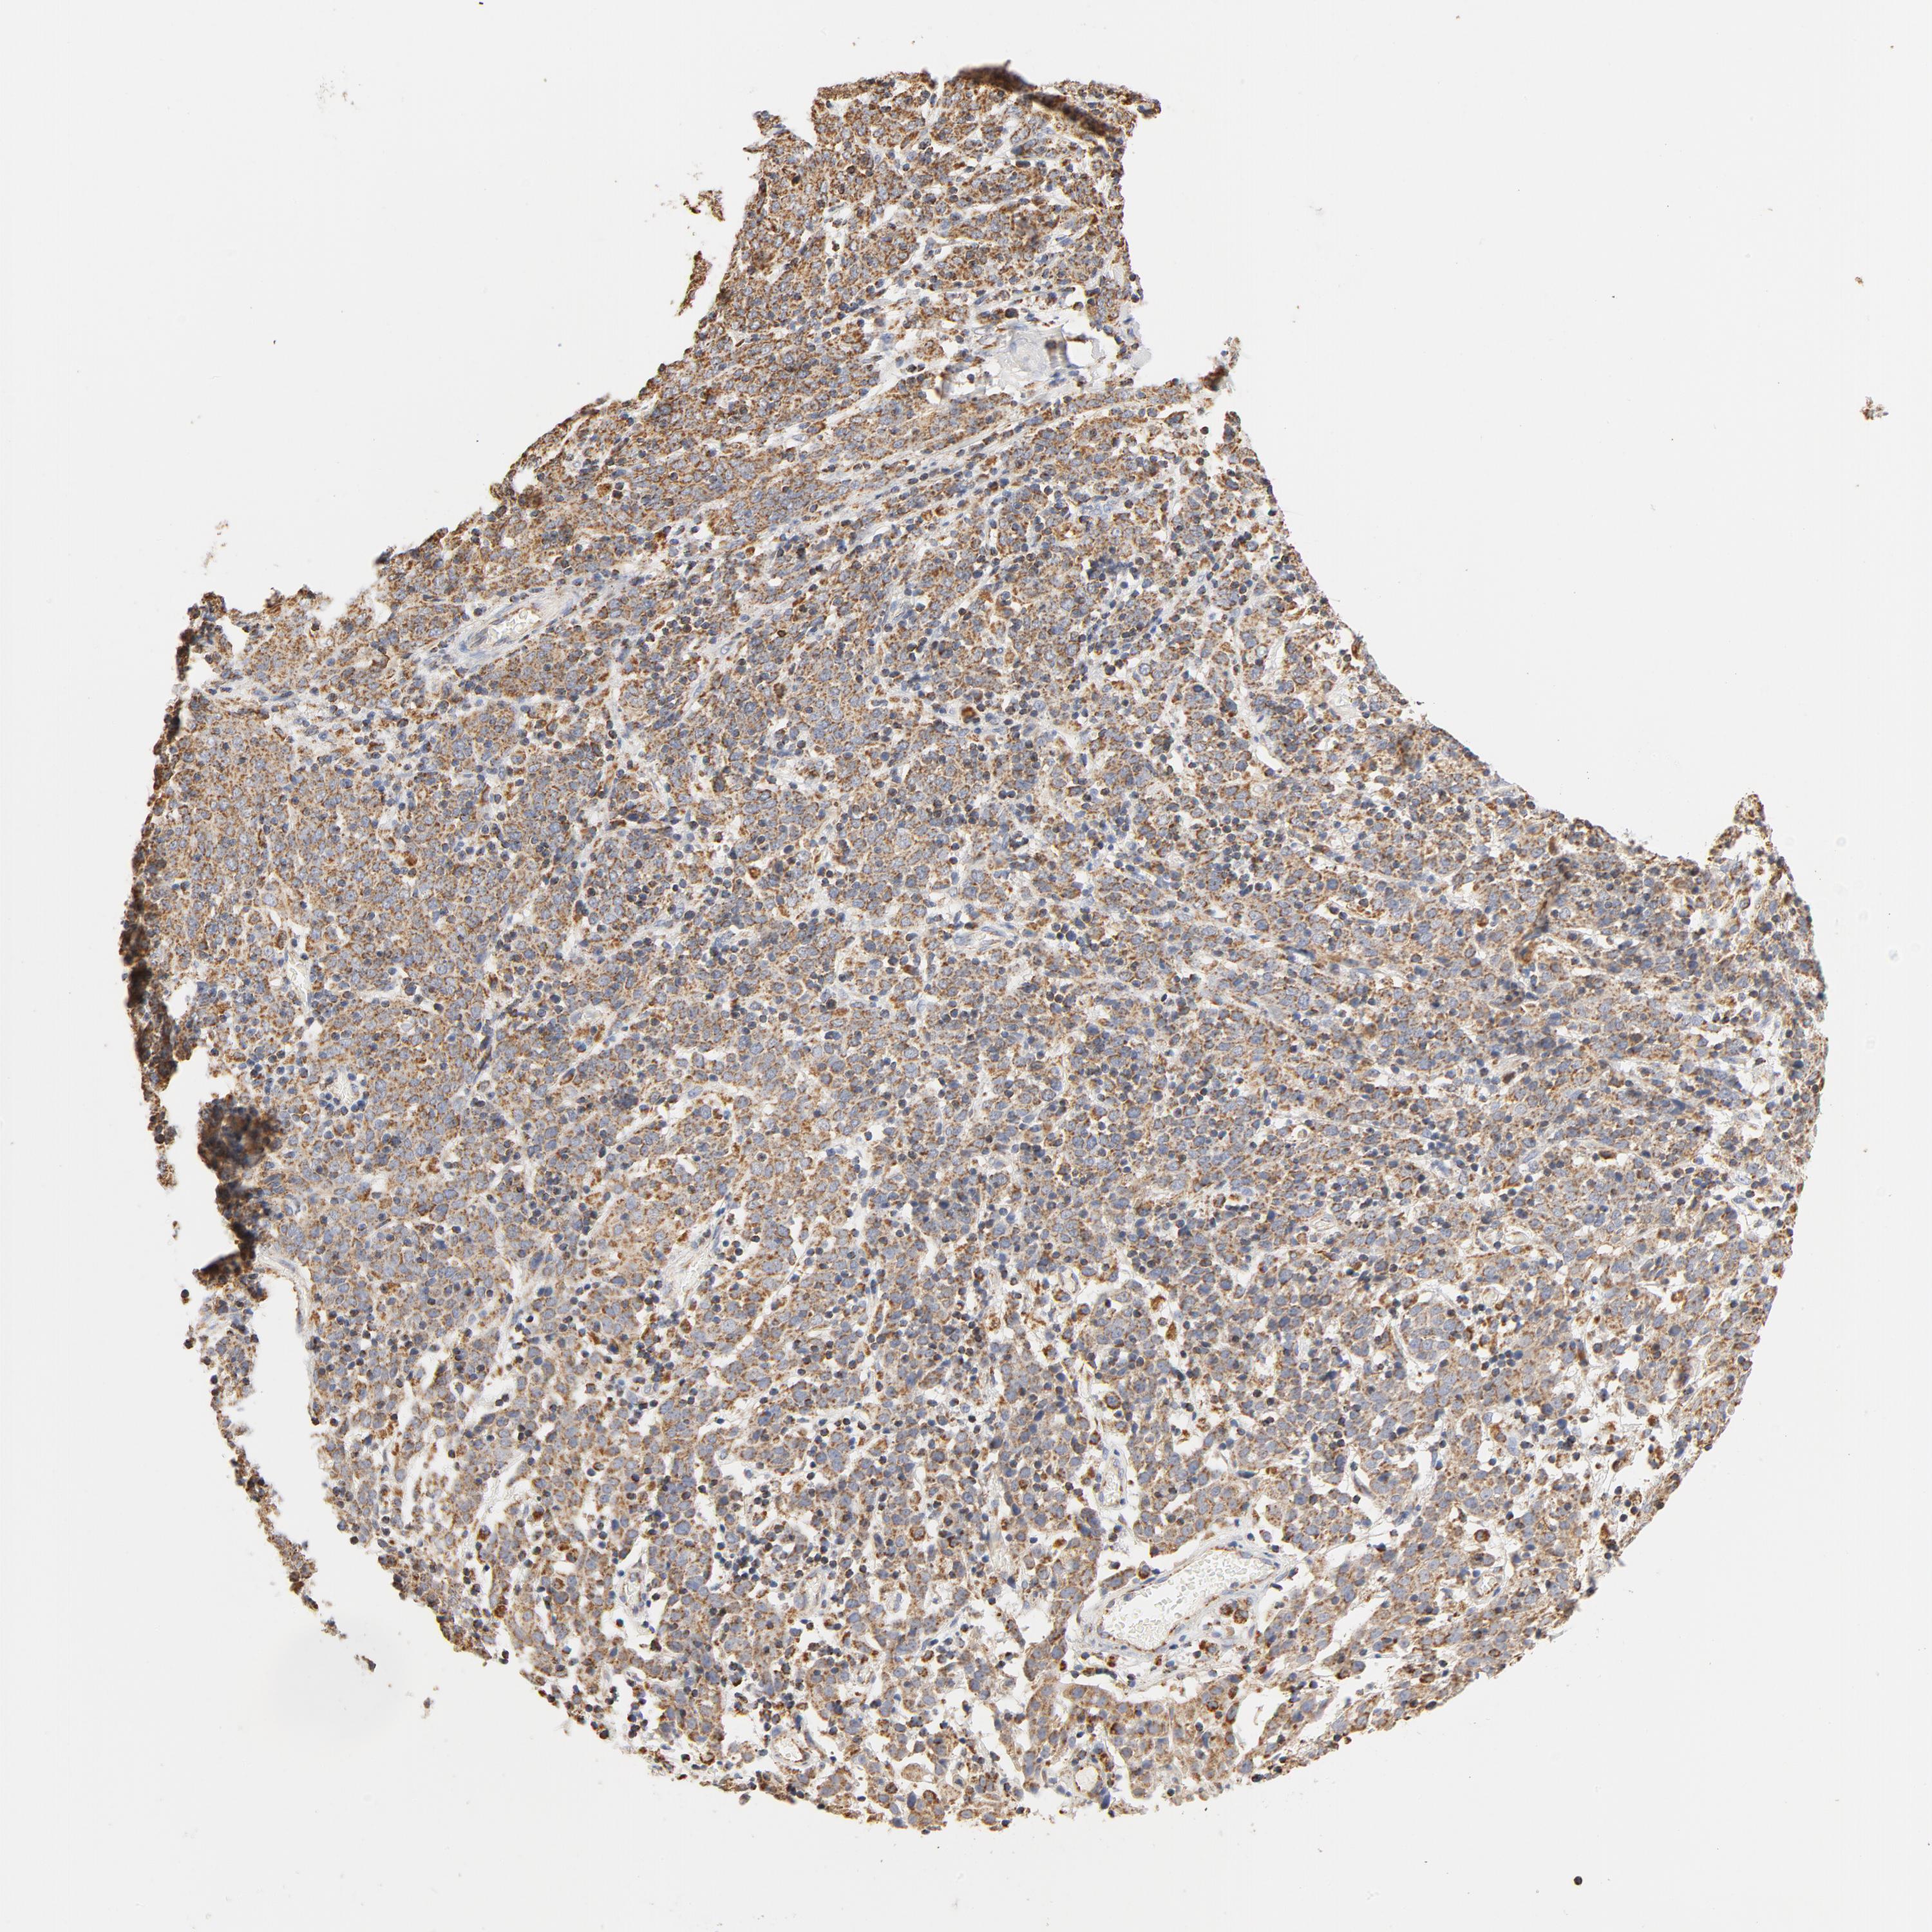

CERVICAL CANCER - Protein expressioni

A mouse-over function shows sample information and annotation data. Click on an image to view it in a full screen mode. Samples can be filtered based on level of antibody staining by selecting one or several of the following categories: high, medium, low and not detected. The assay and annotation is described here.

Note that samples used for immunohistochemistry by the Human Protein Atlas do not correspond to samples in the TCGA dataset.

Antibody stainingi

Antibody staining in the annotated cell types in the current human tissue is reported as not detected, low, medium, or high, based on conventional immunohistochemistry profiling in selected tissues. This score is based on the combination of the staining intensity and fraction of stained cells.

Each image is clickable and will lead to virtual microscopy that enables deeper exploration of all samples and also displays staining intensity scores, fraction scores and subcellular localization as well as patient and tissue information for each sample.

Antibody HPA002485

Antibody CAB004080

Staining

High

Medium

Low

Not detected

Intensity

Strong

Moderate

Weak

Negative

Quantity

>75%

75%-25%

<25%

None

Location

Nuclear

Cytoplasmic/membranous

Cytoplasmic/membranous,nuclear

Squamous cell carcinoma, NOS